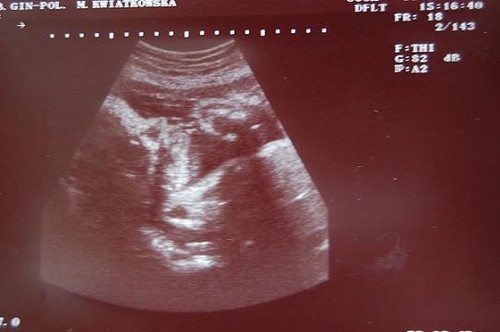

Zobacz załącznik 277546

Kuba wazy 2500. w poniedziałek mam ostatnie ECHO, zeby sprawdzic , czy maly sie obrocil juz ostatecznie. a 6 wrzesnia juz druga wizyte z kraamzorgu...![]()